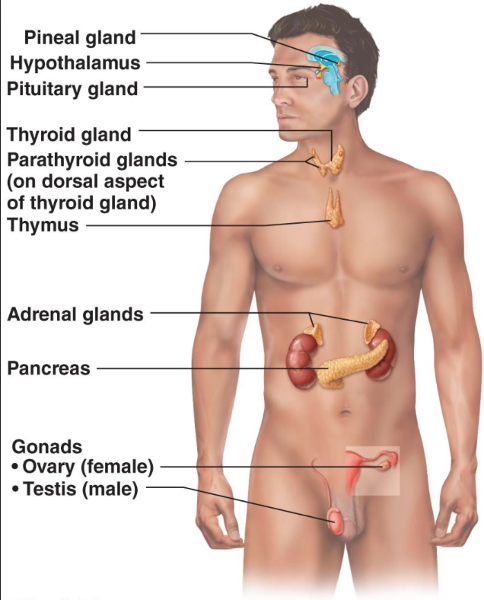

Pituitary Gland

Pineal Gland

Thyroid Gland

Parathyroid Glands-- yellow

Thymus

Adrenal Gland

Pancreas

Gonads